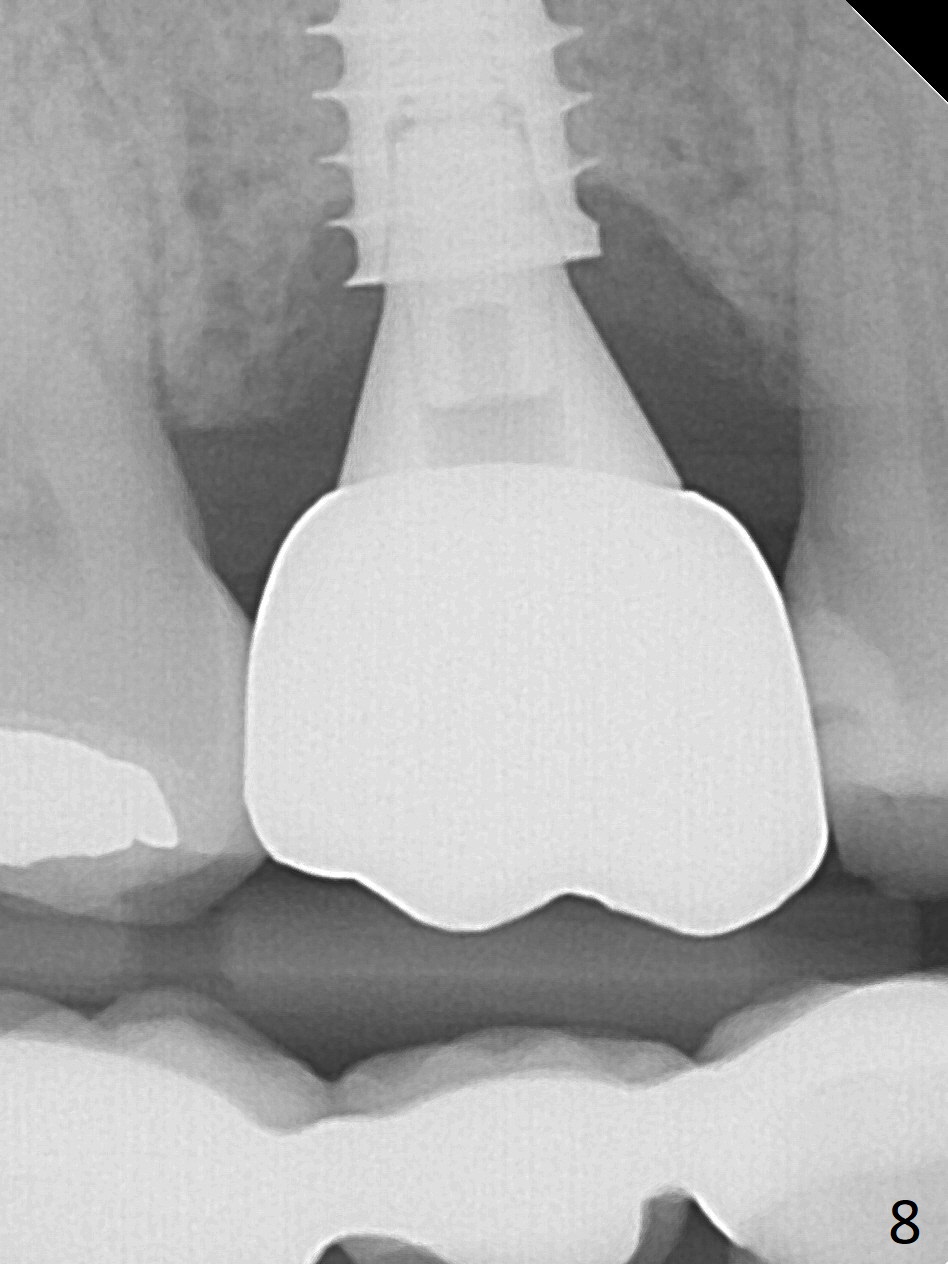

Three weeks postop, the socket has been healing with simultaneous buccal plate collapsing (Fig.5 *, as compared to Fig.2). A larger abutment (7.0-8.5 mm) or a provisional with buccal subgingival margin may decrease the postop shrinking (1,2). There is no bone loss 3 months postop (Fig.6,7). The screw needs to be retightened 9 months post cementation (Fig.8, when the tooth crown is being fabricated at #18). Unilateral mastication is a predisposing factor, since the tooth #19 is missing. When the crown becomes loose again 3 years later, the hex fractures inside the implant. After its removal (Fig.9), a narrower abutment is placed for a new crown (Fig.10: 5x4(4) vs. 6.5x4(4) mm). The implant was placed deep enough without thread exposure; now with apparently complete abutment seating (Fig.11,12). The similar complication may recur due to refusal to have implant at #19 (fear of nerve injury).